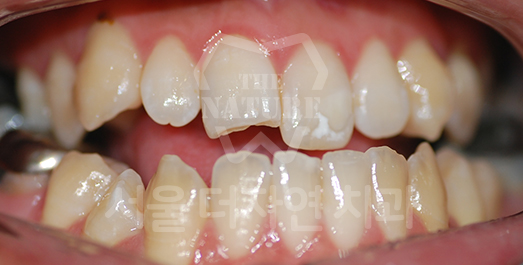

Retrognathia (Receding Chin) Solution

Cases where the maxilla is normal but the mandible is underdeveloped,

and cases where the maxilla is protruded with a normal mandible,

can appear visually similar.

Therefore, accurate diagnosis and a precise treatment plan are essential.

BEFORE: 2012.12.27

AFTER: 2016.04.09